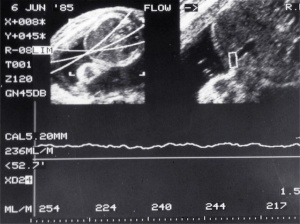

- Umbilical flow measurement (1985)

- Umbilical flow measurement (1986)

Scans – Doppler